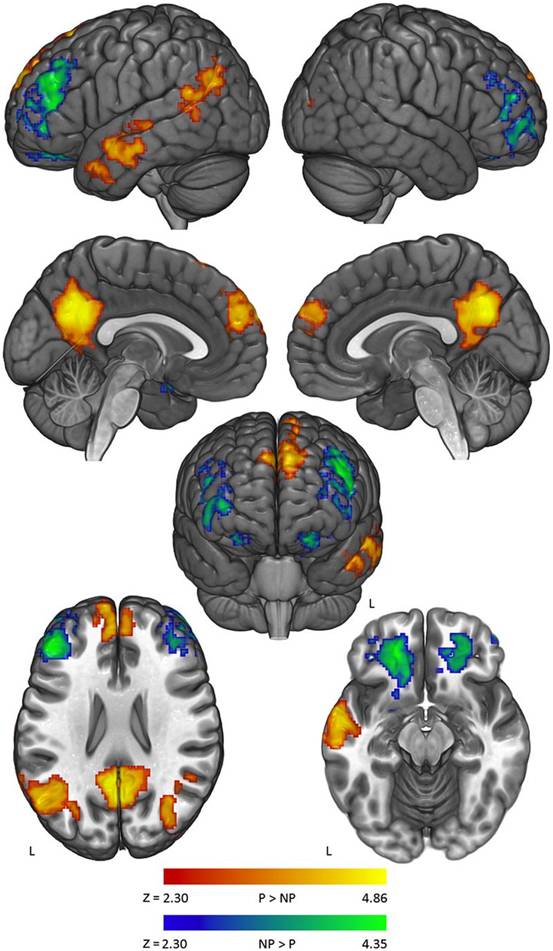

大脑对二者的反应确实不同。存在政治争论时,卡普兰和同事明显看到所谓的“大脑默认网络” (Default Mode Network)变得异常活跃。该区域有关“思维开小差、记忆、思考人生与自我”,卡普兰说。研究还发现,大脑杏仁体的活跃度会增加。杏仁体与人的负面情绪有很大关联。

研究基本能表明,参与者大脑活跃区域都在大脑有关个性和感受威胁的部分。这或许能够说明大脑对不同观点抗拒产生于该区域。